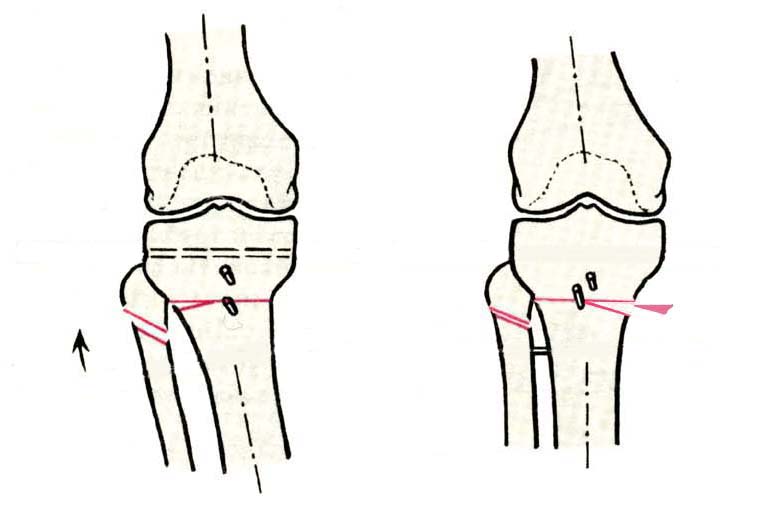

И зачем латерализация периферического фрагмента. Я всегда делаю медиализацию. См схему. И для данного случая медиализация подходит как нельзя лучше.

a> Я всегда делаю медиализацию. См схему. И для данного случая

Медиализация - это чисто эстетический прием, как я понимаю. Поскольку если делать остеотомию ниже вершины деформации, для восстановления оси надо делать смещение по ширине, в данном случае как раз латерализацию.

Картинки - в приложении.Будут вопросы - готов ответить.

Ещё картинка - схема. Хотя у Соломина всё написано.